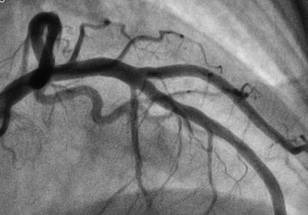

The trial focused on patients with angina, or chest pain due to plaque buildup in the coronary arteries, that is not adequately controlled with available treatments. The CSR is an hourglass-shaped stent designed to narrow the vein that collects blood from the heart muscle (the coronary sinus) and drive oxygen-rich blood back into areas of the heart muscle that may not be receiving enough blood.

All participants had symptomatic angina, ischemia and coronary artery disease with no further medical or interventional options at the start of the study. Participants underwent a cardiac MRI and treadmill exercise test before their procedure and at the end of a blinded six-month follow-up period. Patients also recorded their angina symptoms daily with a smartphone application.